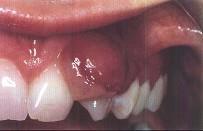

问题 妊娠瘤的临床表现是 ( )

选项 A.以下前牙区唇面龈乳头多见 B.多发生于多个牙的牙间乳头 C.疼痛明显 D.生长慢,质地坚韧 E.妊娠期不能手术切除妊娠瘤

答案 A